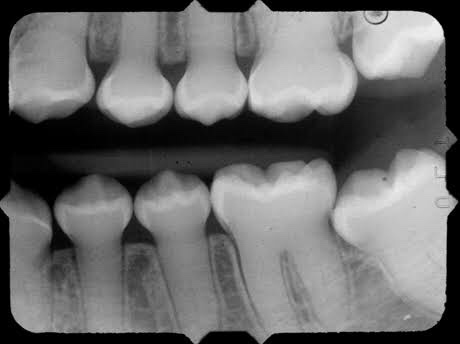

👉🏻 The affected teeth (both dentitions) are grey to yellow brown with broad crowns and constriction at cervical area resulting in tulip shape.

👉🏻 Normal non-mineralized pulp chambers and canals

🔹Radiographic Features: